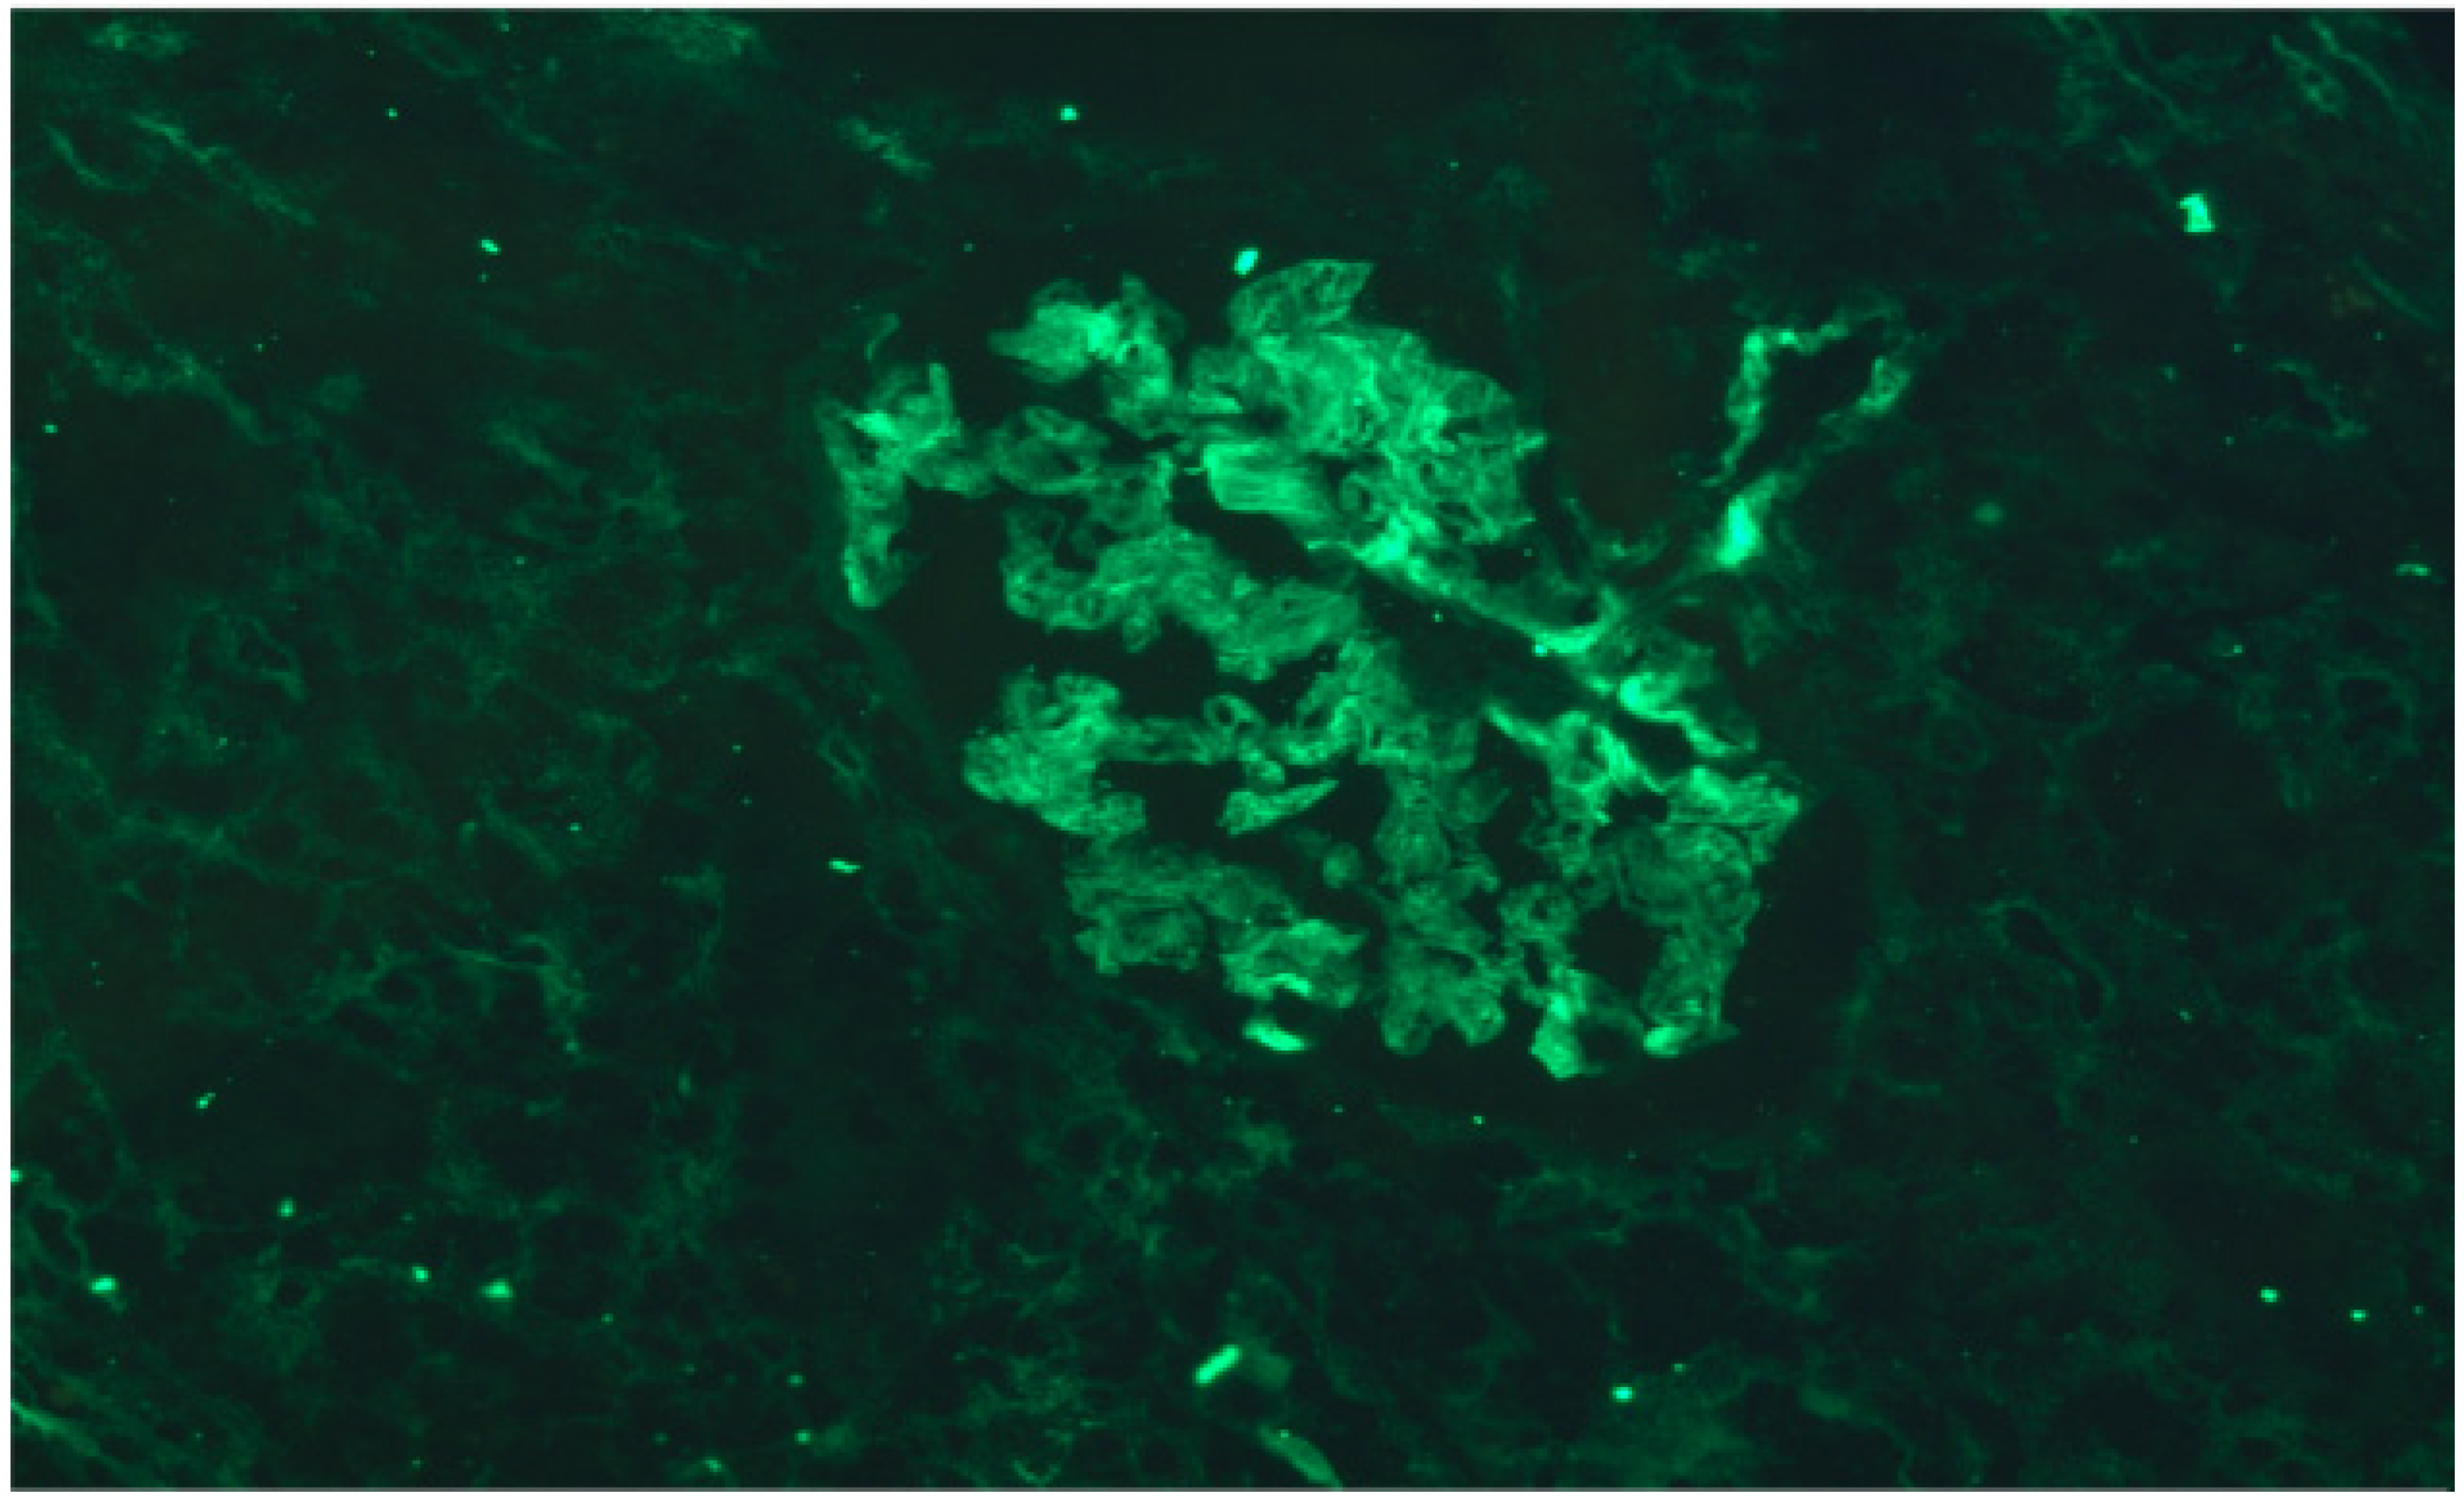

3. Results